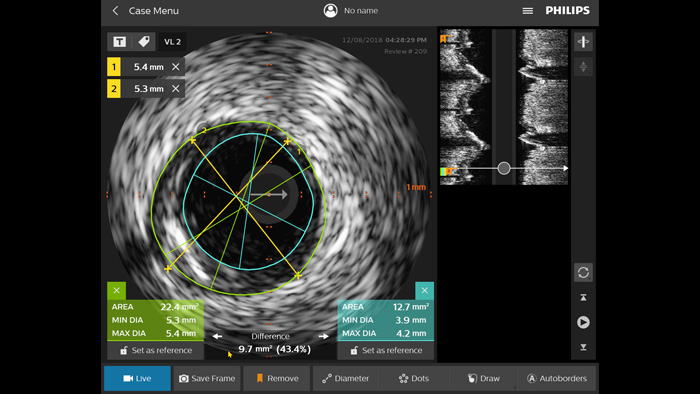

IVUSガイドPCIは標準化された手技であり、患者の転帰を最適化します1,2。

ULTIMATE試験では、IVUSガイドのDES留置は、造影ガイドと比較して、1年のTVFの割合を有意に低下13,14させることが示されています。この試験は3年の追跡まで示されており、IVUSガイドのDES留置はTVFと合わせてステント血栓症の割合が有意に低い13,14ことも示されています。